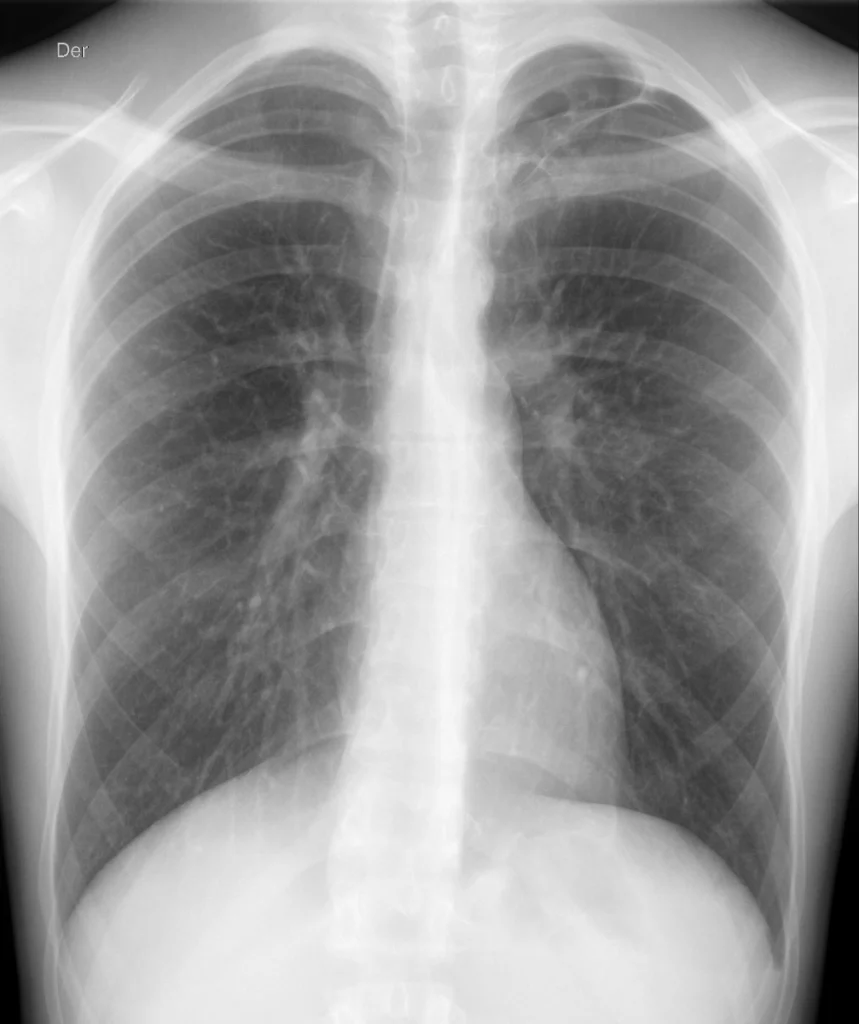

Rx de tórax PA en inspiración. En el ápice izquierdo se observa la hipertransparencia con ausencia completa de trama pulmonar, que indican la presencia de neumotórax. La fina línea radiopaca de la pleura parenquimatosa marca el límite inferior del neumotórax. Mediastino no desplazado.

En este paciente joven, la clínica y el antecedente de un neumotórax un año antes orientaban a un diagnóstico presuntivo de neumotórax izquierdo. Sí bien era ya evidente en la proyección PA en máxima inspiración, en fase de espiración evidenció una mayor extensión del mismo. La proyección en espiración aumenta las posibilidades de identificar incluso neumotórax de pequeño volumen. Recuerda valorar la posición del mediastino: un mediastino desplazado hacia el lado contrario indica un neumotórax a tensión y requiere tratamiento urgente.